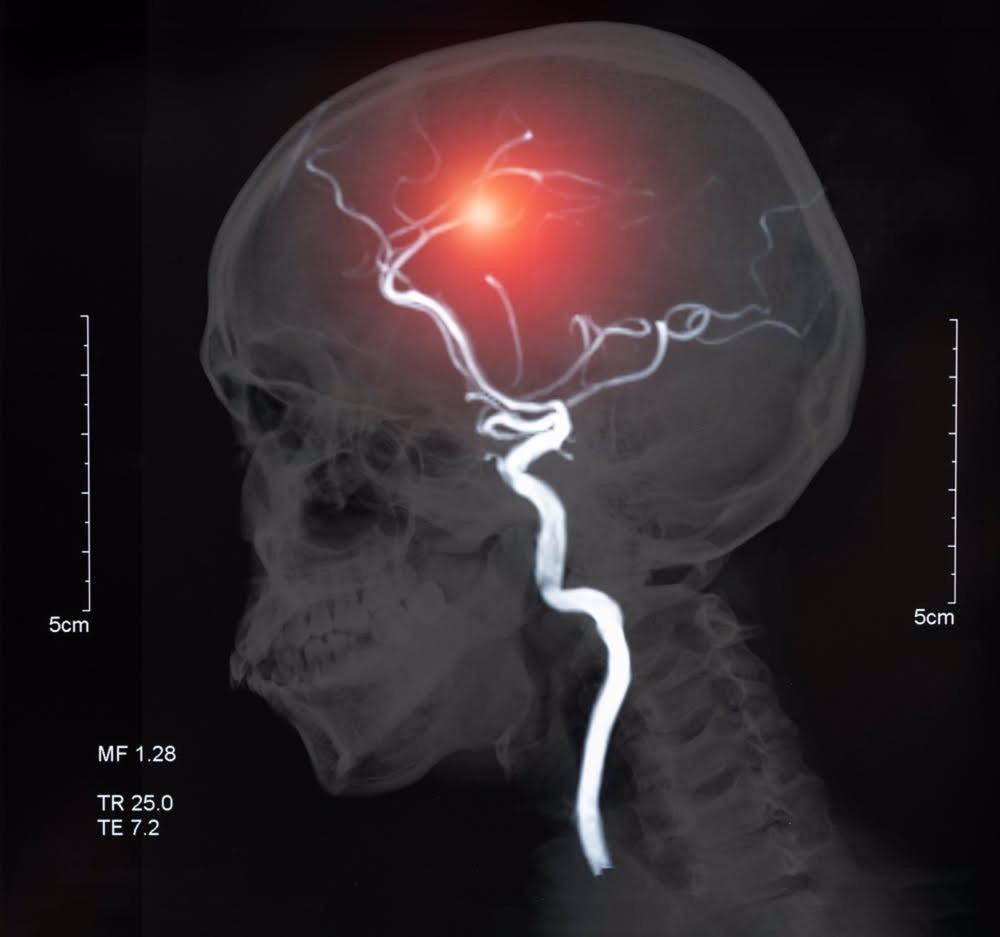

En este sentido, la trombectomía endovascular es un tratamiento no quirúrgico cada vez más utilizado para el accidente cerebrovascular isquémico, en el que se insertan microcatéteres o tubos delgados visibles con rayos X en el coágulo de sangre para disolverlo.

«Una desventaja potencial de este tratamiento, ahora ampliamente utilizado y efectivo, es que el rápido retorno del suministro de sangre a un área que ha estado privada de oxígeno durante un tiempo puede causar daño tisular conocido como lesión por reperfusión», han detallado los expertos.